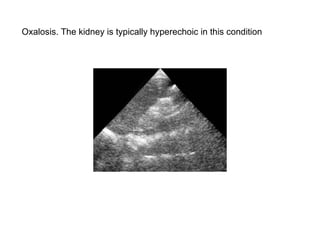

Oxalosis. The kidney is typically hyperechoic in this condition